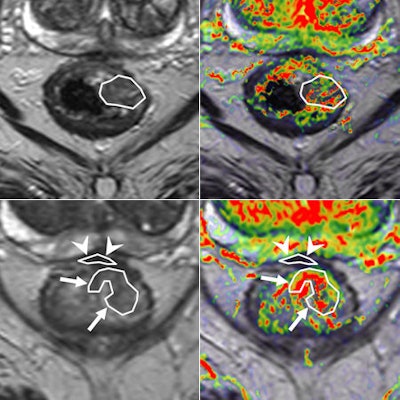

Same case as above. Histopathology confirmed the areas of residual tumor (arrows) and fibrosis (arrowheads).

Dose shaping gives rise to a need for ever more accurate imaging that identifies a tumor's heterogeneity and for imaging to evaluate response both during and after radiotherapy. Radiation oncologists want to know from radiologists which regions in the tumor are more resistant to their treatment and how these regions are responding during the radiation treatment so that the dose can be adapted, Beets-Tan stated.

Size alone is inefficient as a radiotherapy response evaluation tool, because it can mislead at times and is less accurate than functional and metabolic imaging, and she thinks PET and MRI have capabilities to offer improved imaging in this respect. MRI has the advantage of showing a high resolution of morphology, but also functional imaging of tumor biology and behavior, she pointed out.

Imaging biomarkers, in particular, can provide an objective measure of pathophysiological processes.

"This is why I think the future of MR imaging will involve diffusion, perfusion, proliferation and, further into the future still, hypoxia and automated image segmentation," Beets-Tan said. "This is where we radiologists will have a significant role in our collaboration with radiation oncologists."